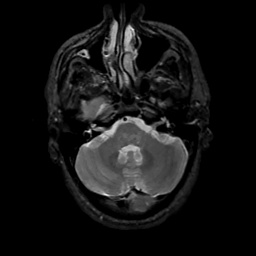

MR Study #13, May 19, 1991 -- Slice #11